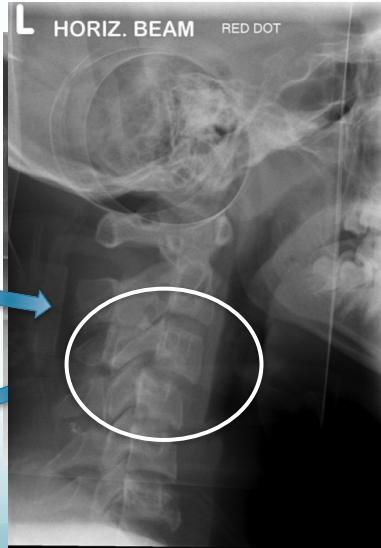

Burst Injury L-Spine

- Axial compression: shattered vertebral body

- Posterior fragments into spinal canal

- Usually unstable

- CT required

Burst Injury Classification

Is this a compression or a burst fracture?

- A burst fracture

- Why?

- Posterior displacement